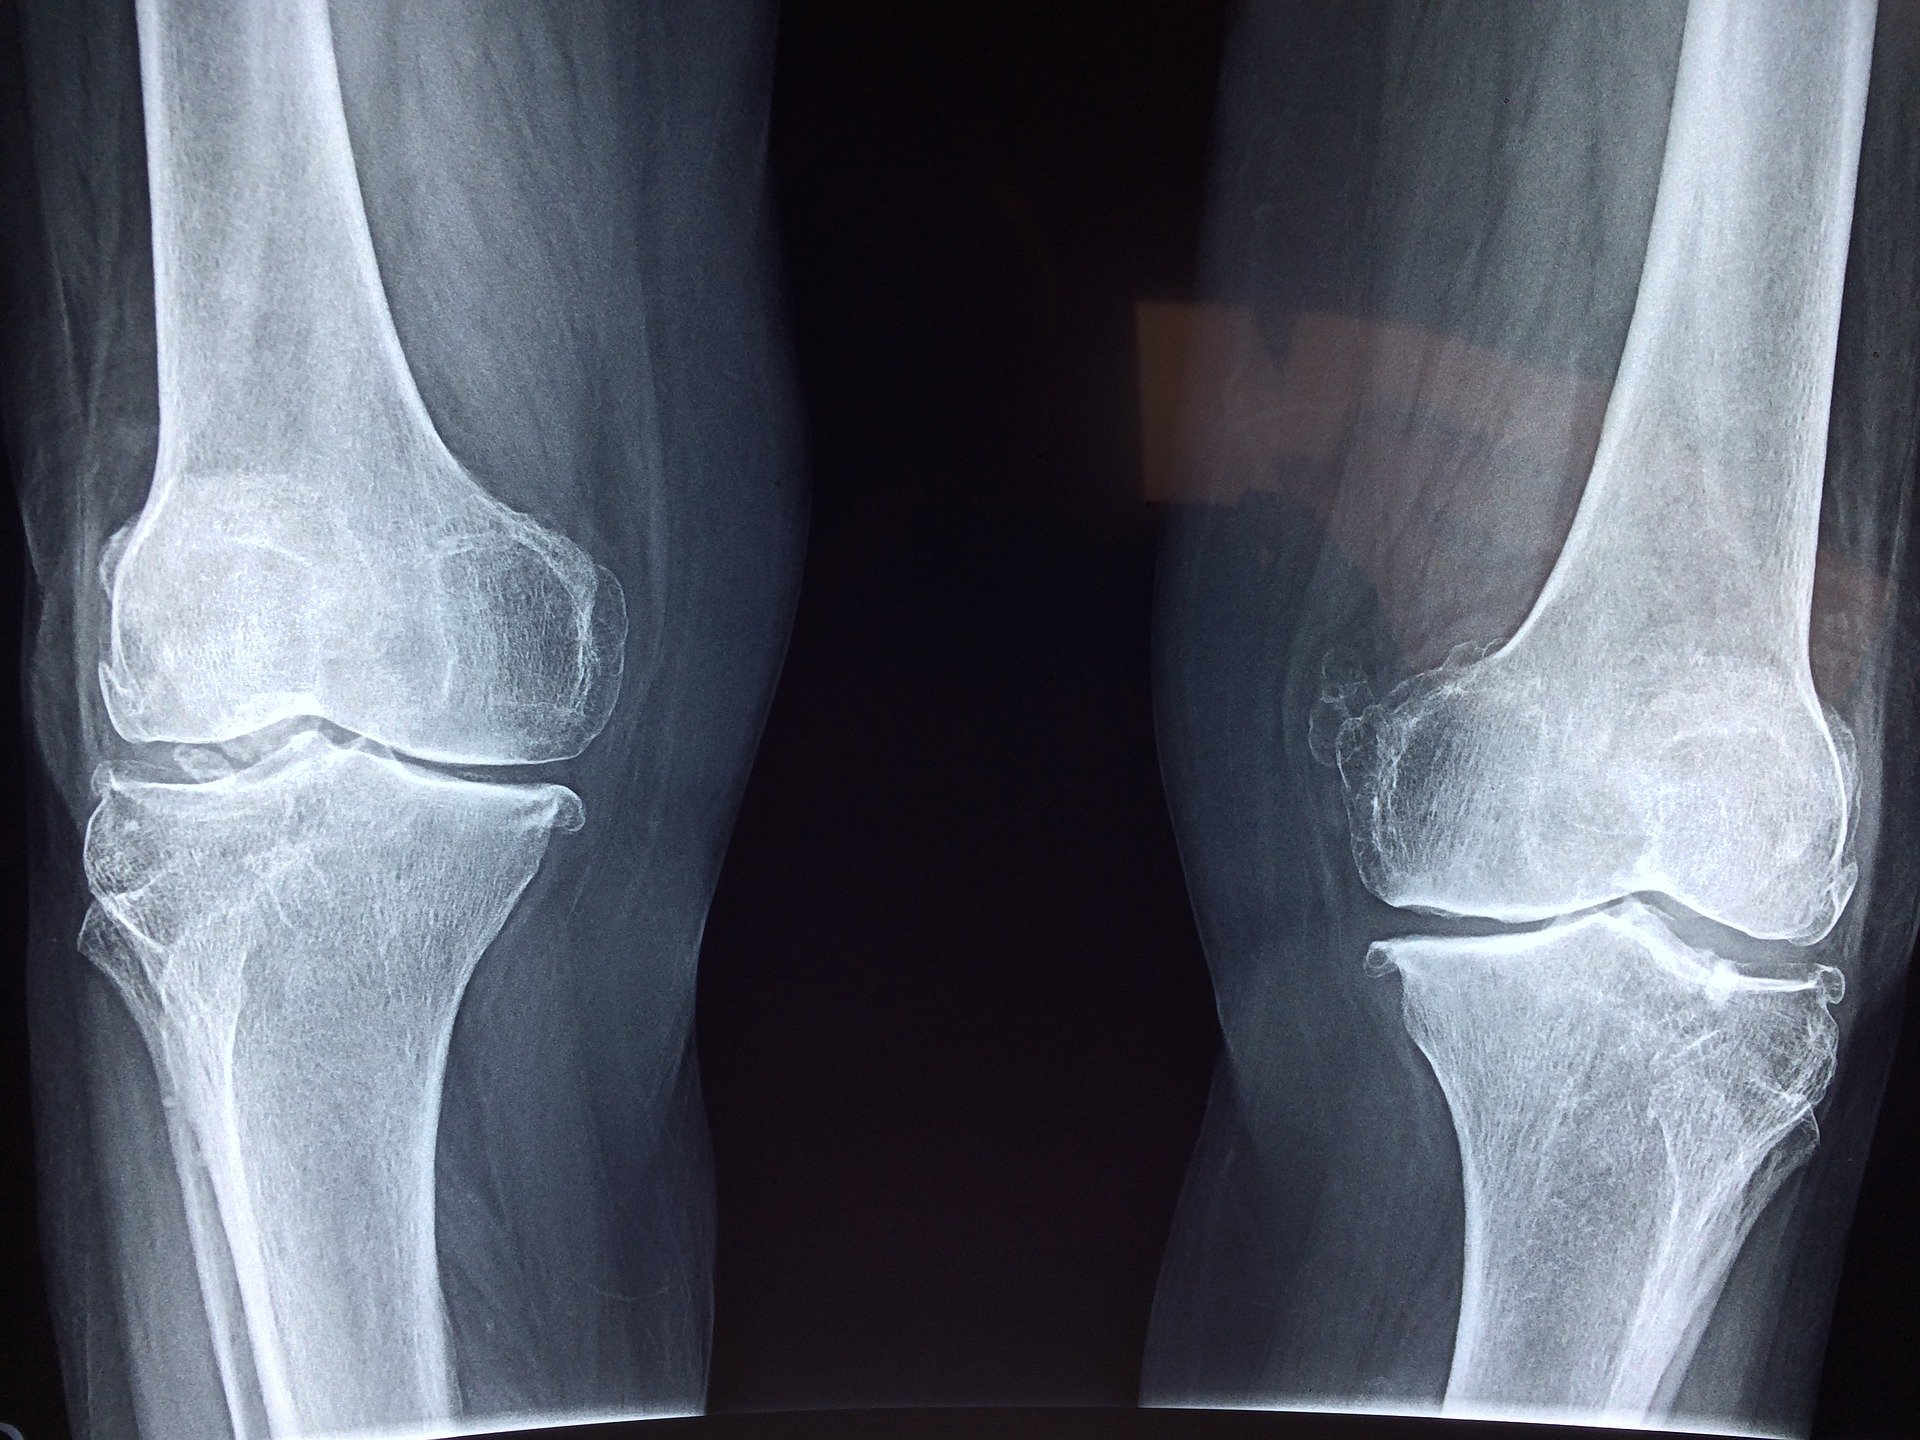

Niewiarygodne. Domowe metody, które przynoszą ulgę i łagodzą objawy bólu kolan.

Czy znałeś tajemny klucz do Twojego codziennego funkcjonowania, który zazwyczaj jest ignorowany? Tak, to są Twoje kolana! Często dopiero kiedy ból staje się nieznośny i ogranicza nasz ruch, zaczynamy na nie zwracać uwagę.

Więc co robisz, gdy ból kolan jest intensywny, kolano puchnie, a do lekarza jest daleko?